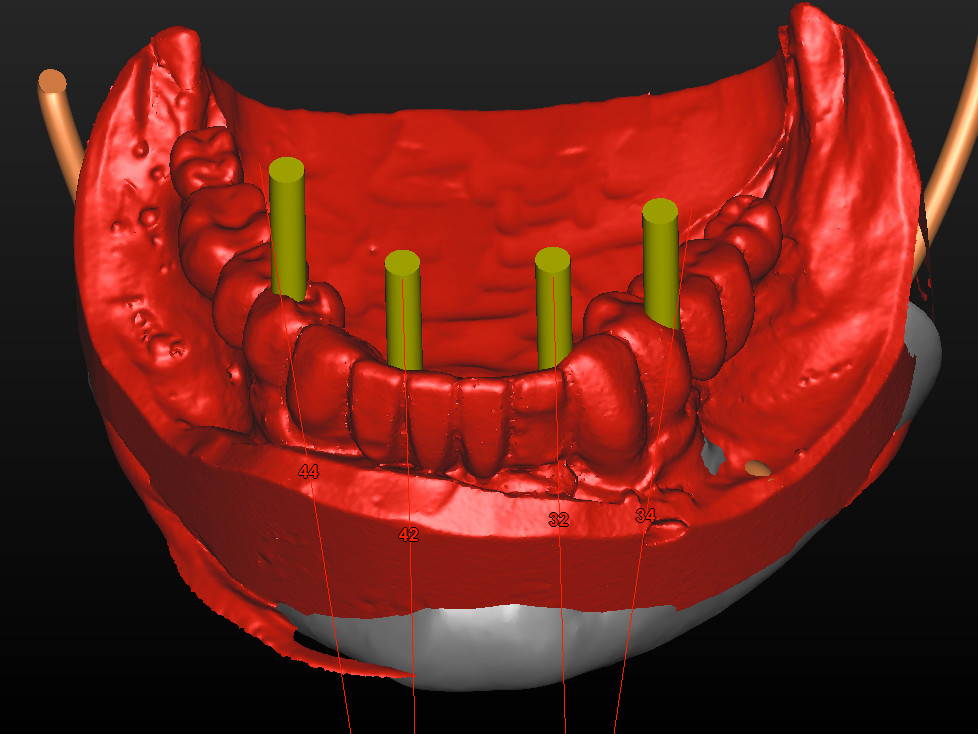

Bei dem nachfolgenden Fall handelt es sich um eine 73-jährige Nichtraucherin im guten allgemeinen Gesundheits- und Ernährungszustand. Die Patientin steht in keiner medikamentösen Behandlung und wies keine Allergien auf. Die Patientin kam 2012 zu uns in die Behandlung. Damals zeigte sich bei ihr eine festsitzende aber insuffiziente Rehabilitation im Unterkiefer, wobei die beiden Blattimplantate die gesamte Rekonstruktion trugen. Die Unterkieferzähne, die bisher die anteriore Abstützung bildeten, waren unter der prothetischen Versorgung kariös zerstört (Abb. 1). Seitens der Patientin bestand der Wunsch nach hochwertiger Rehabilitation des Unterkiefers möglichst mit einer Sofortversorgung. Eine zwischenzeitliche Versorgung mit einer schleimhautgetragenen Interimsprothese schied aus. Darüber hinaus war für die Patientin wichtig, eine möglichst geringe Belastung durch die anstehende Behandlung zu erfahren. Der Oberkiefer war mit eine herausnehmbaren Vollprothese rehabilitiert. Zur exakten Vorhersagbarkeit der Implantatpositionen wurde ein DVT angefertigt. Im Anschluss erfolgte eine gemeinsame Planung der chirurgischen sowie prothetischen Implantatposition im Team, bei der Chirurg, Prothetiker und Zahntechniker im ständigen Dialog standen (Abb. 2 und 3).

Mit dem Digital Immediate Smile Model von Materialise Dental ist es erstmals möglich, die aus der DVT-Planung stammenden Daten als offenen STL-Export zu erhalten. Neben der Information über die Position der Implantate und den dazugehörigen Abutments enthält der STL-Export auch „gematchte“ Optical Scan Modelle (Situationsmodelle) (Abb. 4), die mit vielen CAD-Programmen weiterverarbeitet werden können. Zudem wird dem zahntechnischen Labor ermöglicht, ohne Zeitdruck präoperativ ein Sofortprovisorium zu erstellen. In diesem Fall wurden die STL Daten in eine CAD Software geladen. Die Modellation des Provisoriums erfolgte anhand des Situationsscans (Abb. 5). Die verwendeten Retentionskappen für das Ankylos® C/X Implantatsystem wurden virtuell in der CAD Software hinterlegt und mit einem zusätzlichen Platzhalter versehen. Nach Fertigstellung des Designprozesses wurde das Sofortprovisorium auf einer fünfachsigen Fräsmaschine gefertigt und anschließend poliert (Abb. 6). Ferner wurden die Retentionskappen mit 120μm Aluminiumdioxid zur Retentionsvergrößerung angestrahlt. Das so gefertigte Sofortprovisorium wird nach dem chirurgischen Eingriff in der „Passive-Fit-Technik“⁷ intraoral verklebt, um etwaige Abweichungen der Implantatachse und –tiefe auszugleichen und eine Spannungsfreiheit zu gewährleisten⁸.